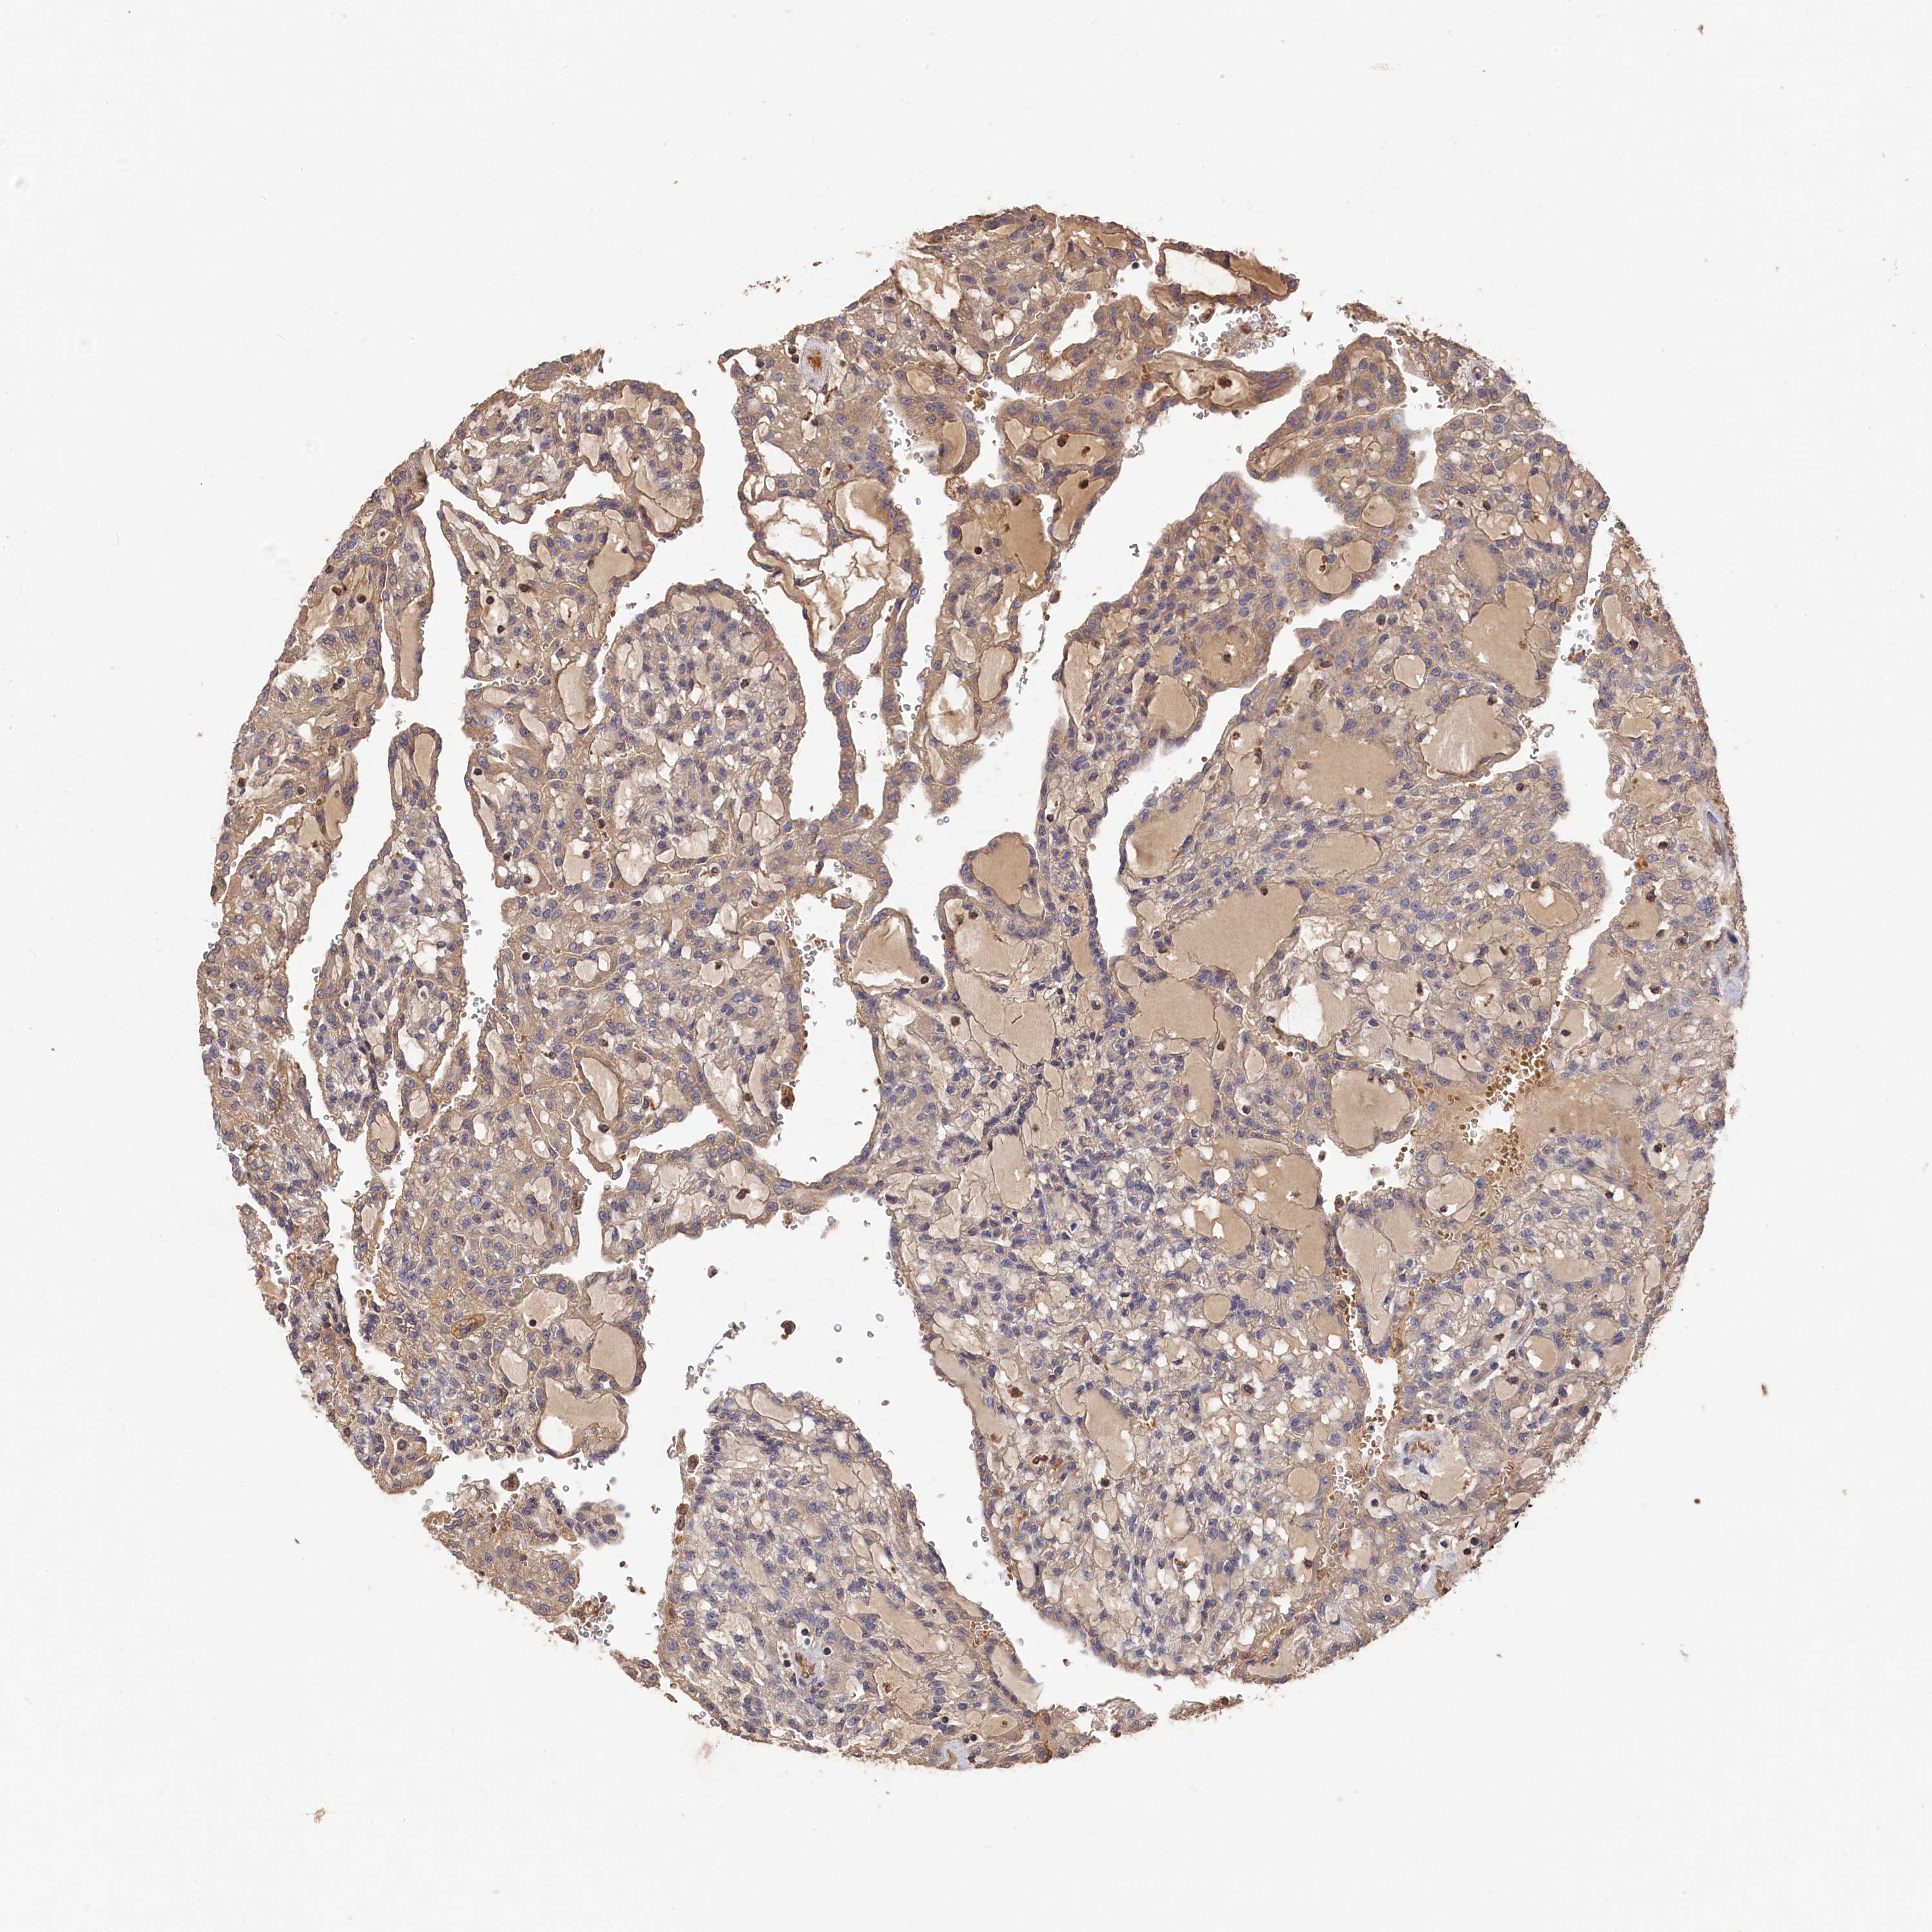

KIDNEY RENAL CLEAR CELL CARCINOMA (VALIDATION) - Interactive survival scatter ploti

The Survival Scatter plot shows the clinical status (i.e. dead or alive) for all individuals in the patient cohort, based on the same data that underlies the corresponding Kaplan-Meier plots. Patients that are alive at last time for follow-up are shown in blue and patients who have died during the study are shown in red.

The x-axis shows the expression levels (FPKM) of the investigated gene in the tumor tissue at the time of diagnosis. The y-axis shows the follow-up time after diagnosis (years). Both axes are complimented with kernel density curves demonstrating the data density over the axes. The top density plot shows the expression levels (FPKM) distribution among dead (red) and alive patients (blue). The right density plot shows the data density of the survived years of dead patients with high and low expression levels respectively, stratified using the cutoff indicated by the vertical dashed line through the Survival Scatter plot. This cutoff is automatically defined based on the FPKM cutoff that minimizes the p-score. The cutoff can be changed by dragging the vertical line or by entering a cutoff value in the square labeled "Current cut-off".

Under the Survival Scatter plot the p-score landscape (black curve; left axis) is shown together with dead median separation (red curve; right axis). Dead median separation is the difference in median mRNA expression between patients who have died with high and low expression, respectively. It is calculated as follows: median FPKM expression of dead patients with high expression - median FPKM expression of dead patients with low expression. This is intended to aid the user in visually exploring custom cutoffs and the associated p-scores and dead median separation.

Individual patient data is displayed and can be filtered by clicking on one or more of the category buttons on the top of the page. Categories describing expression level and patient information include: high, low, alive, dead, female, male and tumor stages. The scale of the x-axis can be toggled between linear and log-scale by clicking on the "x log" button. Mouse-over function shows TCGA ID, patient information and mRNA expression (FPKM) for each patient.

& Survival analysisi

Kaplan-Meier plots summarize results from analysis of correlation between mRNA expression level and patient survival. Patients were divided based on level of expression into one of the two groups "low" (under cut off) or "high" (over cut off). X-axis shows time for survival (years) and y-axis shows the probability of survival, where 1.0 corresponds to 100 percent.

DHRS11 is not prognostic in Kidney Renal Clear Cell Carcinoma (validation)

Best expression cut offi

Based on the FPKM value of each gene, patients were classified into two groups and association between prognosis (survival) and gene expression (FPKM) was examined. The best expression cut-off refers the FPKM value that yields maximal difference with regard to survival between the two groups at the lowest log-rank P-value. Best expression cut-off was selected based on survival analysis .

When clicking on this number, the vertical dashed line indicating cut-off, the interactive survival plot, and the Kaplan-Meier curve will be adjusted to show results based on the best expression cut-off.

: 4.72

P scorei

Log-rank P value for Kaplan-Meier plot showing results from analysis of correlation between mRNA expression level and patient survival.

N/A

TCGA RNA samplesi

RNA-seq data is reported as average FPKM (number Fragments Per Kilobase of exon per Million reads), generated by the The Cancer Genome Atlas (TCGA) .

Normal distribution across the dataset is visualized with box plots, shown as median and 25th and 75th percentiles. Points are displayed as outliers if they are above or below 1.5 times the interquartile range. FPKM values of the individual samples are presented next to the box plot.

Average pTPM 4.5

Number of samples 100